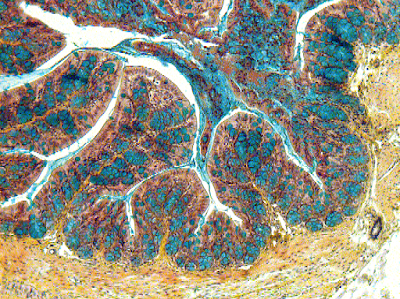

Continúa explicando "se ensayó su efecto terapéutico en varios modelos preclínicos de enfermedad inflamatoria intestinal y se observó que era incluso más efectiva que los tratamientos de referencia actuales usados en clínicas para estos pacientes, como son infliximab y mesalazine.

"Aquí utilizando información estructural de resonancia magnética nuclear, diseñamos cinco análogos de cortistatina adoptando conformaciones seleccionadas de cortistatina nativa en solución. Uno de ellos, A5, conserva las actividades antiinflamatorias e inmunomoduladoras de cortistatina "in vitro" y en modelos de la enfermedad en ratón", explicaban los investigadores.

La molécula A5, también muestra una vida media aumentada en suero y un característico perfil de unión al receptor, lo que supera las limitaciones de cortistatina nativa como un agente terapéutico. "Este estudio proporciona un enfoque eficiente para el diseño racional de los análogos de cortistatina y abre nuevas posibilidades para el tratamiento de los pacientes que no responden a otras terapias" explicaban los investigadores.